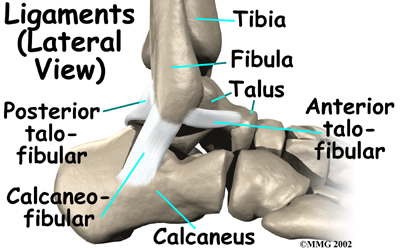

Anatomy

What part of the ankle is involved?

Ligaments are tough bands of tissue that help connect bones together. make up the lateral ligament complex on the side of the ankle farthest from the other ankle. They are the anterior talofibular ligament (ATFL), the calcaneofibular ligament (CFL), and the posterior talofibular ligament (PTFL). The common inversion injury to the ankle usually involves , the ATFL and CFL. Normally, the ATFL keeps the ankle from sliding forward, and the CFL keeps the ankle from rolling inward on its side.